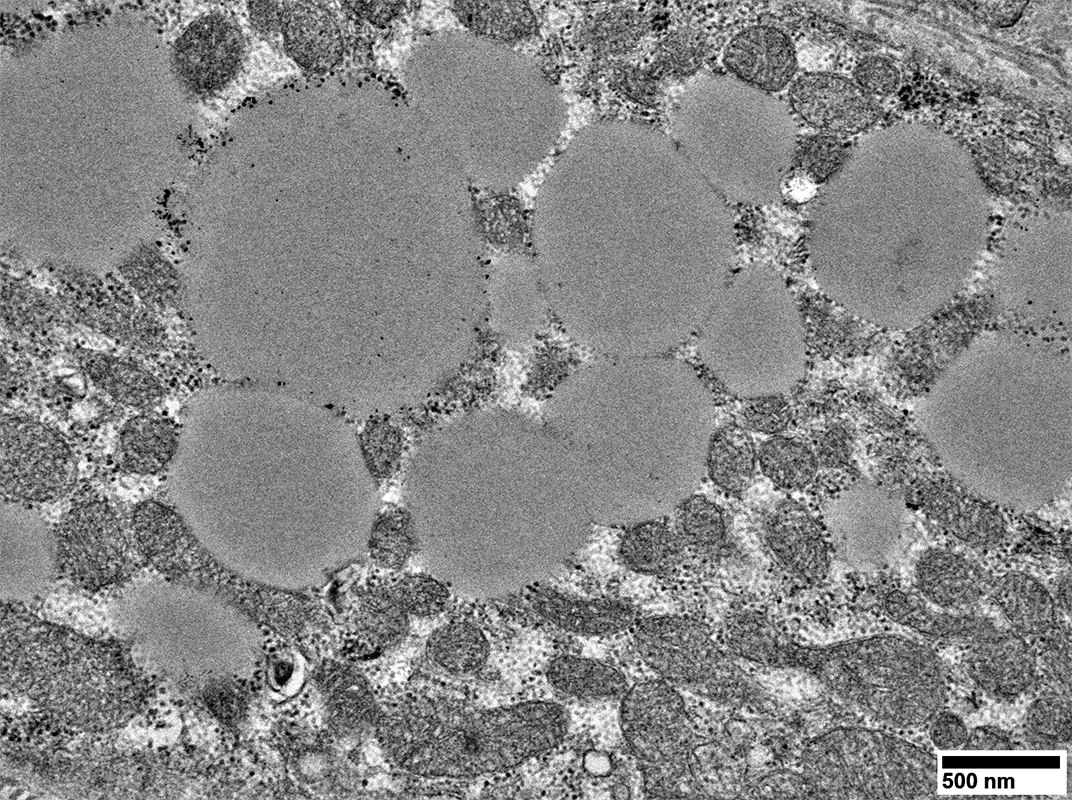

MELAS: Mitochondrial Ultrastructure

From: R Schmidt